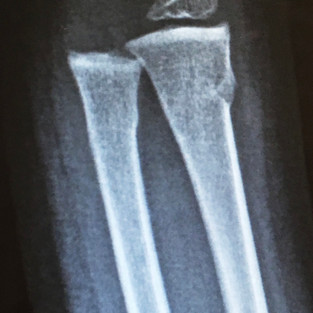

Dan jokes that he attempted to “Superman” off the trampoline. In reality, while we have a fairly safe trampoline (safety net around it), accidents can and do still happen. He went to get off of it and managed to trip over the mat that covers the springs- so he tried to catch himself to keep from face planting in the gravel (trampoline is next to driveway). The result was a buckle fracture of both the radius and ulna.

He had his cast taken off right are 4 weeks this past Monday. They did a repeat X-ray (sorry/ no pic of that one) and said he doesn’t even need the splint that they thought he'd need. Yay for the 3 year old being able to resume all normal activities- including normal bathing! Hooray!